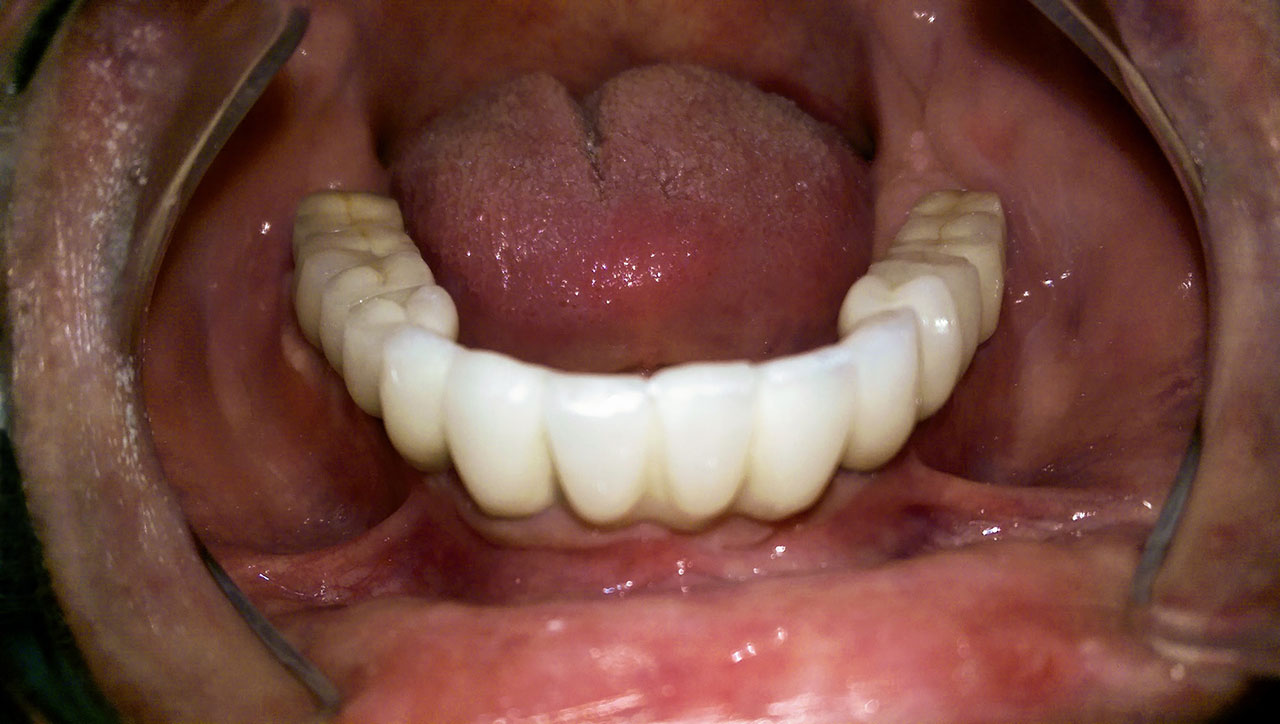

Alsó állcsont teljes rehabilitációja 72 óra alatt

Alsó állcsont teljes rehabilitációja 72 óra alatt, azonnal terhelhető implantátumokkal súlyos paradontitisben szenvedő dohányzó páciens esetében. Az alsó állcsont fogai mind mozogtak az előrehaladott fogágypusztulás miatt.

A fogakat eltávolítottuk, a gyulladt, fertőzött csontot kitakarítottuk, kifertőtlenítettük, majd azonnal implantáltunk.

Svájci, IHDE márkájú, azonnal terhelhető implantátumokat helyzetünk be, és ezekre harmadnapra rögzített, hosszútávú, fémvázas, esztétikus műanyaggal leplezett hidat ragasztottunk be.

Ezt az ideiglenes hidat a sebek gyógyulása miatt használjuk, de tartóssága miatt véglegesként is használható.

A legtöbb esetben, ahogy itt is, 6 hónap múlva porcelán hídra cseréljük, a teljes gyógyulás után.